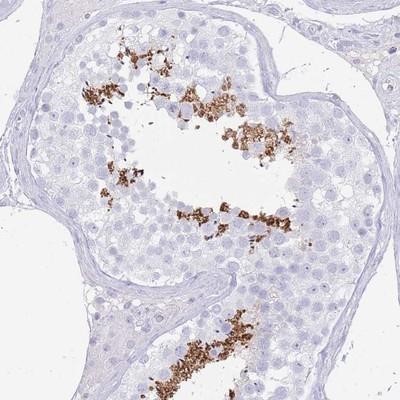

- Immunohistochemistry-Paraffin: C2orf57 Antibody [NBP2-14406] - Staining of human testis shows high expression.